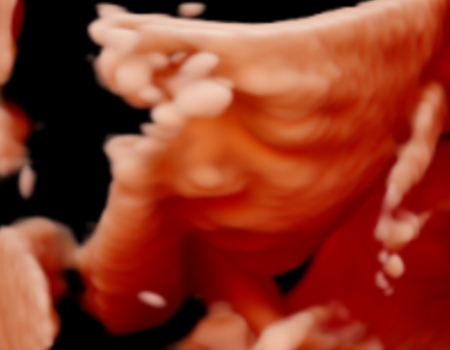

¡La ecografía 5D es una imagen en tres dimensiones y en tiempo real, como la 4D, pero en la que el tratamiento de las imágenes en el ordenador permite suavizar las texturas, modificar el color de la imagen y aplicar un foco de luz desde diferentes ángulos de forma que se crean luces y sombras y esto le da una imagen más real.

La Ecografía 5D incorpora un procesamiento más avanzado que optimiza la iluminación, la textura y la profundidad de la imagen, logrando una representación más clara y uniforme del bebé. Gracias a estos ajustes, los rasgos faciales y los movimientos se aprecian con mayor naturalidad, reduciendo imperfecciones visuales propias de otras modalidades y ofreciendo una imagen final más definida y comprensible para las familias.